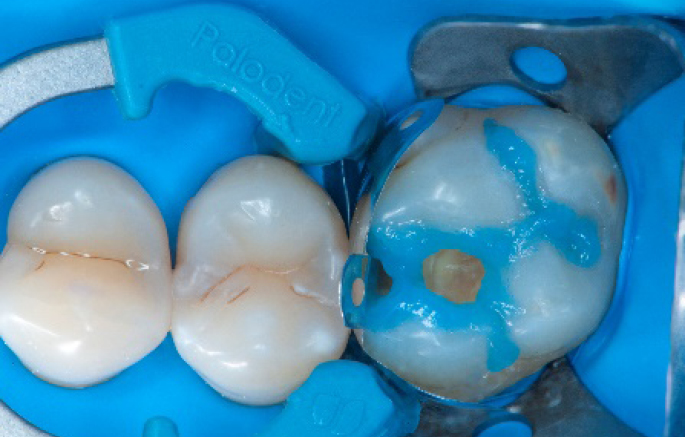

Step 1:

The situation after rubber dam isolation.

Step 4:

The complete Palodent1 system in place: sectional matrix, wedge and ring.

Step 5:

Buccal view of the Palodent1 system.